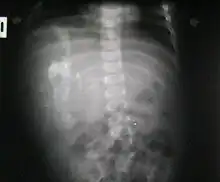

Fetus in fetu

Fetus in fetu (or foetus in foetu) is a rare developmental abnormality in which a mass of tissue resembling a fetus forms inside the body of its twin. An early example of the phenomenon was described in 1808 by George William Young.[1]

There are two hypotheses for the origin of a "fetus in fetu". One hypothesis is that the mass begins as a normal fetus but becomes enveloped inside its twin.[2] The other hypothesis is that the mass is a highly developed teratoma. "Fetus in fetu" is estimated to occur in 1 in 500,000 live births.[3]